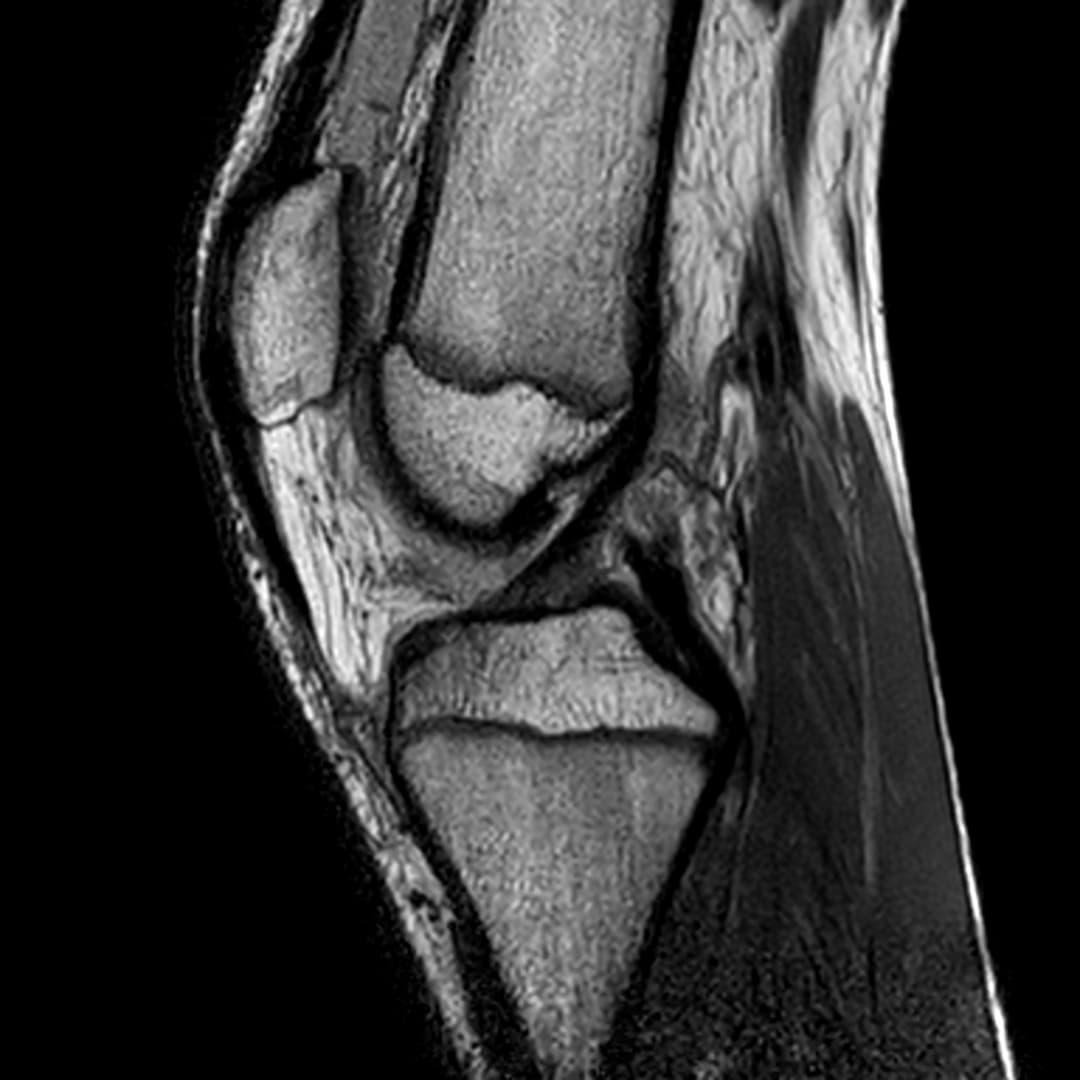

Contusion osteo-chondrale du genou

Présentation clinique

Douleurs post traumatique et gonflements

IRM

Intégrité ligamentaire et méniscale

Fracture sous chondrale par impaction avec œdème sous chondral en miroir du compartiment fémoro-tibial médial.

Epanchement articulaire abondant.